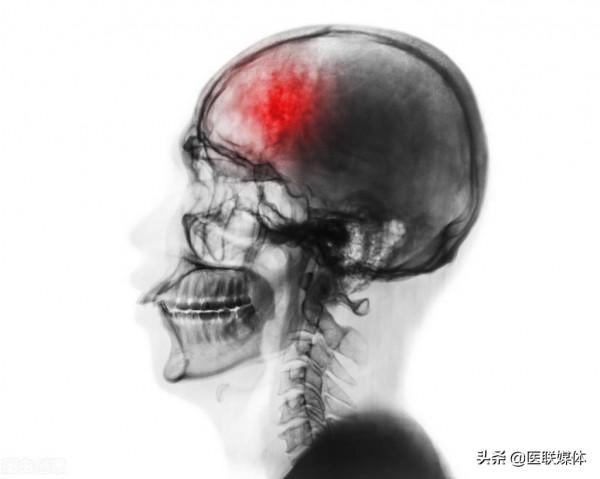

說到腦中風相信很多人不陌生,這種情況多出現在中老年人身上。本身年齡增長就容易讓器官功能降低,血管也脆性增大,彈性降低,甚至有迴圈受阻的可能,如果沒有積極調養,保持各項指標穩定,嚴重疾病會盯上。那麼,腦中風高發是否很可怕呢

腦中風作為危害程度較高的疾病,無論是大腦部位的血管堵塞,狹窄,還是血管破裂,出血,都會威脅患者的生命健康,有的人治療不及時還留下了多種後遺症,相比其他普通疾病來說更可怕,發展迅猛,可提供搶救的時間並不多,因此要認真預防,注意血管養護。